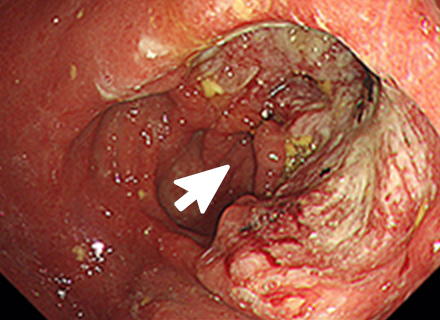

早期胃がんの内視鏡的治療

内視鏡治療の対象となる胃がんは、病変が一括で取れる部位と大きさであり、リンパ節転移の可能性がほとんどないほぼ粘膜内にとどまっていると診断された早期胃がんになります。

内視鏡的治療が外科手術に比べ優れた点は、入院期間が短い上に、おなかに傷がつかず、大きな併発症がなければ退院後の食生活、社会生活に支障がないことです。劣っている点は、切除した組織の状態によっては遺残病変の有無が確認困難な場合があり、将来再発する可能性があることや、切り取った病変の組織検査の結果、局所にがん細胞が残っている可能性がある場合や、がんがリンパ節に転移している可能性があると判断された場合は、さらに外科手術が必要になることです。

内視鏡を使った早期胃がんの治療法には、内視鏡的粘膜切除術(EMR)と内視鏡的粘膜下層剥離術(ESD)の2種類があります。

内視鏡的粘膜切除術:EMR(Endoscopic mucosal resection)

スネアと呼ばれる金属の輪を病変部に引っ掛け、高周波電流を流して病変を切り取ります。EMRは、治療が比較的短時間ですみますが、一度に切り取ることができる病変の大きさは、スネアの大きさ(約2cm)までと制限があります。

内視鏡的粘膜下層剥離術:ESD(Endoscopic submucosal dissection)

専用の処置具を使いより広範囲に病変を切り取ることが可能な治療法です。切り取られた病変は、最終的に顕微鏡でその組織の様子が確認されます(病理検査)。この方法では、大きな病変をひとかたまりで取り、病理検査でより正確な診断を行うことができます。

ESDは大きな病変も一括して切除可能ですが、手技が煩雑で時間がかかり、出血や穿孔などの併発症が生じる場合があります。ほとんどの場合内視鏡的に止血可能ですが、稀には輸血、開腹手術などを要することがあります。